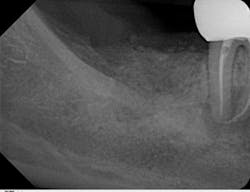

The old saying “you don’t know what you don't know” holds especially true in regard to 3-D radiology. You simply cannot gain the same amount of information from 2-D images. My main use for CBCT in the general dentistry practice is dental implant planning. In order to feel confident placing dental implants, I need this technology. I am able to identify cases that are appropriate for my skill level, as well as cases that are more difficult and should be referred. Whether a case will be tricky is not always obvious from a 2-D image and clinical exam. I also have not found a situation where less information was more beneficial than more information. I have never thought to myself, “I wish I didn’t have a 3-D scan of this patient.” Conversely, there were many times before buying my CBCT when I wished I had more than just a 2-D periapical (PA) or pan. The case shown in figures 1, 2, and 3 illustrates how the additional information CBCT provides aids in planning and placing dental implants.

I also use my ProMax 3D Classic for endodontic evaluation and treatment when needed (figures 6–8). A small field of view (5 cm x 5 cm) image can be taken to limit radiation exposure and focus on the tooth in question. It has come in handy when looking for the second mesiobuccal (MB2) canal in maxillary molars and makes identifying periradicular lesions much easier than periapical radiographs.